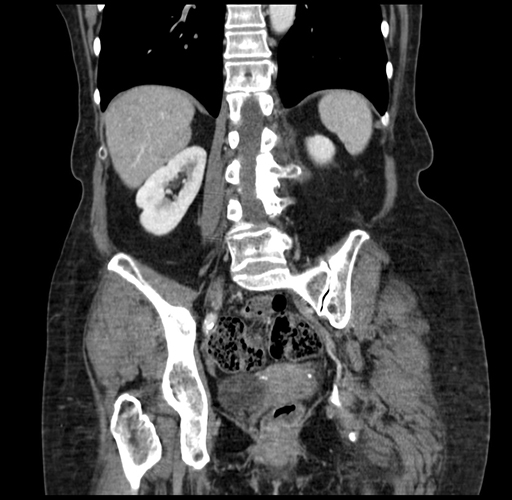

Pre-Chemo: Coronal Venous

Coronal Venous